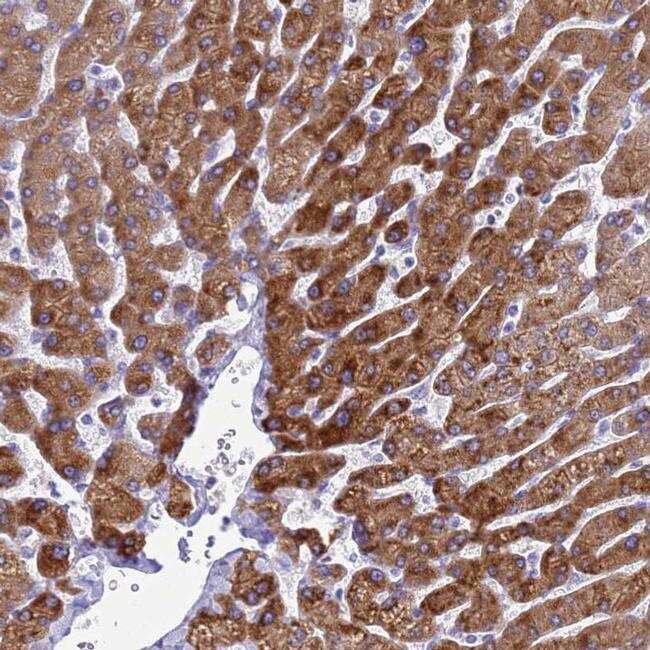

- Immunohistochemical analysis of KNCN in human liver using KNCN Polyclonal Antibody (Product # PA5-61224) shows strong cytoplasmic positivity in hepatocytes.